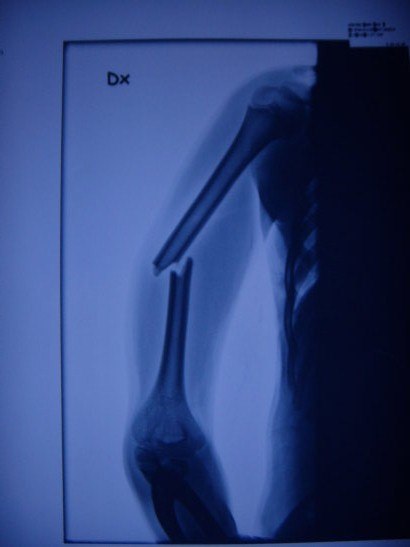

Min brors arm efter han hade testat sideflip i mediumhoppet i tandå superpark.

Johan

tandådalen (

Tandådalen/Hundfjället